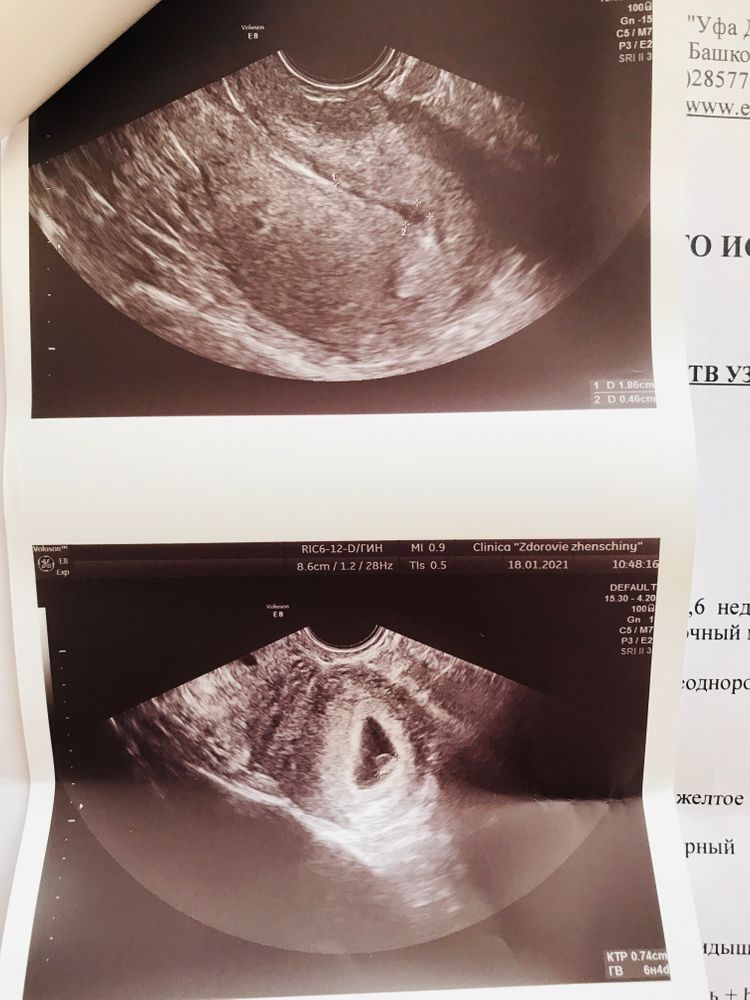

Нашли мою крошку, но и нашли гематому..

УЗИ, КТГ, доплерДевочки сходила сегодня на узи в другую клинику, все хорошо. Врач спросила если ли в родстве двойняшки.. я сказала нет, потом она мне говорит похоже на ПЯ но нет это сгусток. Так вот гематома вроде как ни страшно, читала что ничего не нужно делать должна сама пройти.. врачу написала он сказал приехать для назначения лечения, какое лечение утрожестан ставить что ли? У многих читала гинекологов пишут что если ничего не беспокоит не болит живот и нет выделений то ничего не нужно делать просто наблюдать, напишите пожалуйста как у вас было?

18.01.2021